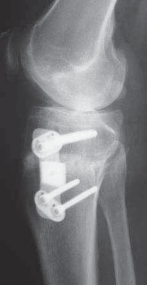

A C B D TECH FIG 7•A.

B.

Intraoperative final AP radiograph.

C,D.

Postoperative AP and lateral radiographs.